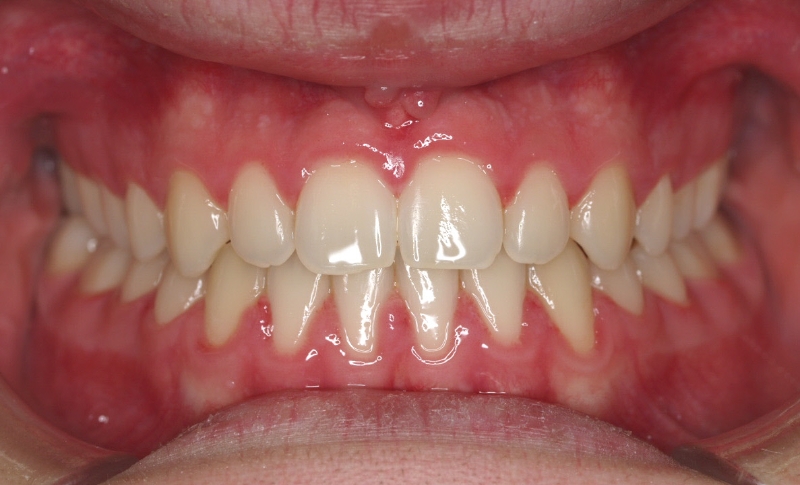

El paciente E.A. acude a nuestra consulta por diastema inferior y ausencia de contactos en los sectores laterales.

1) Arreglamos el problema funcional (lengua baja). Colaboramos con la logopeda Ana Muñoz.

2) Colocamos aparatología fija (brackets Damon) arriba y abajo.